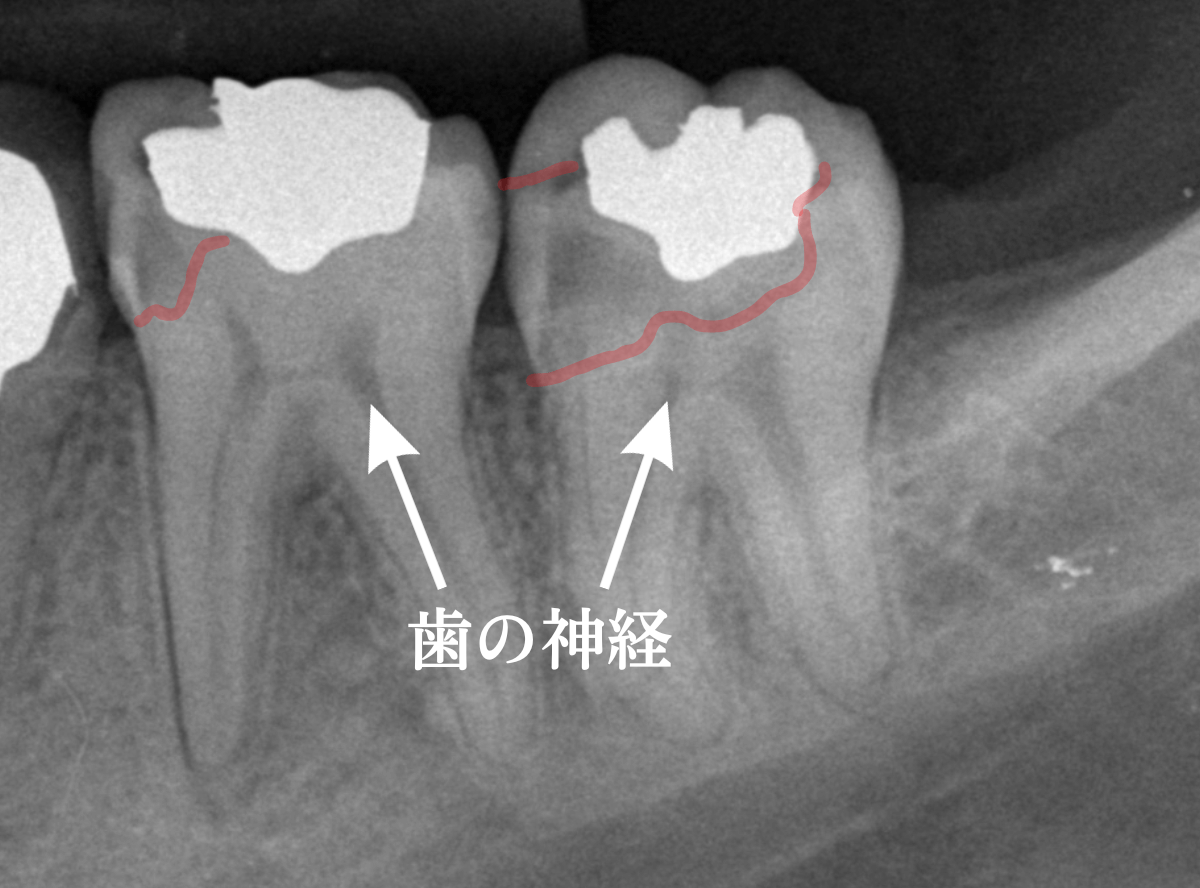

レントゲン写真で確認します。

やはり、奥歯の端が大きな虫歯になっています。

青いラインが歯の神経、赤いラインが虫歯です。

レントゲン写真上では虫歯が神経まで達しているように見えます。

これは、神経を取らないとダメかもしれません。

青い線が神経で、赤い線が虫歯と思われる部分です。

奥から3歯が虫歯と思われますが、特に中央の歯の虫歯が深そうです。